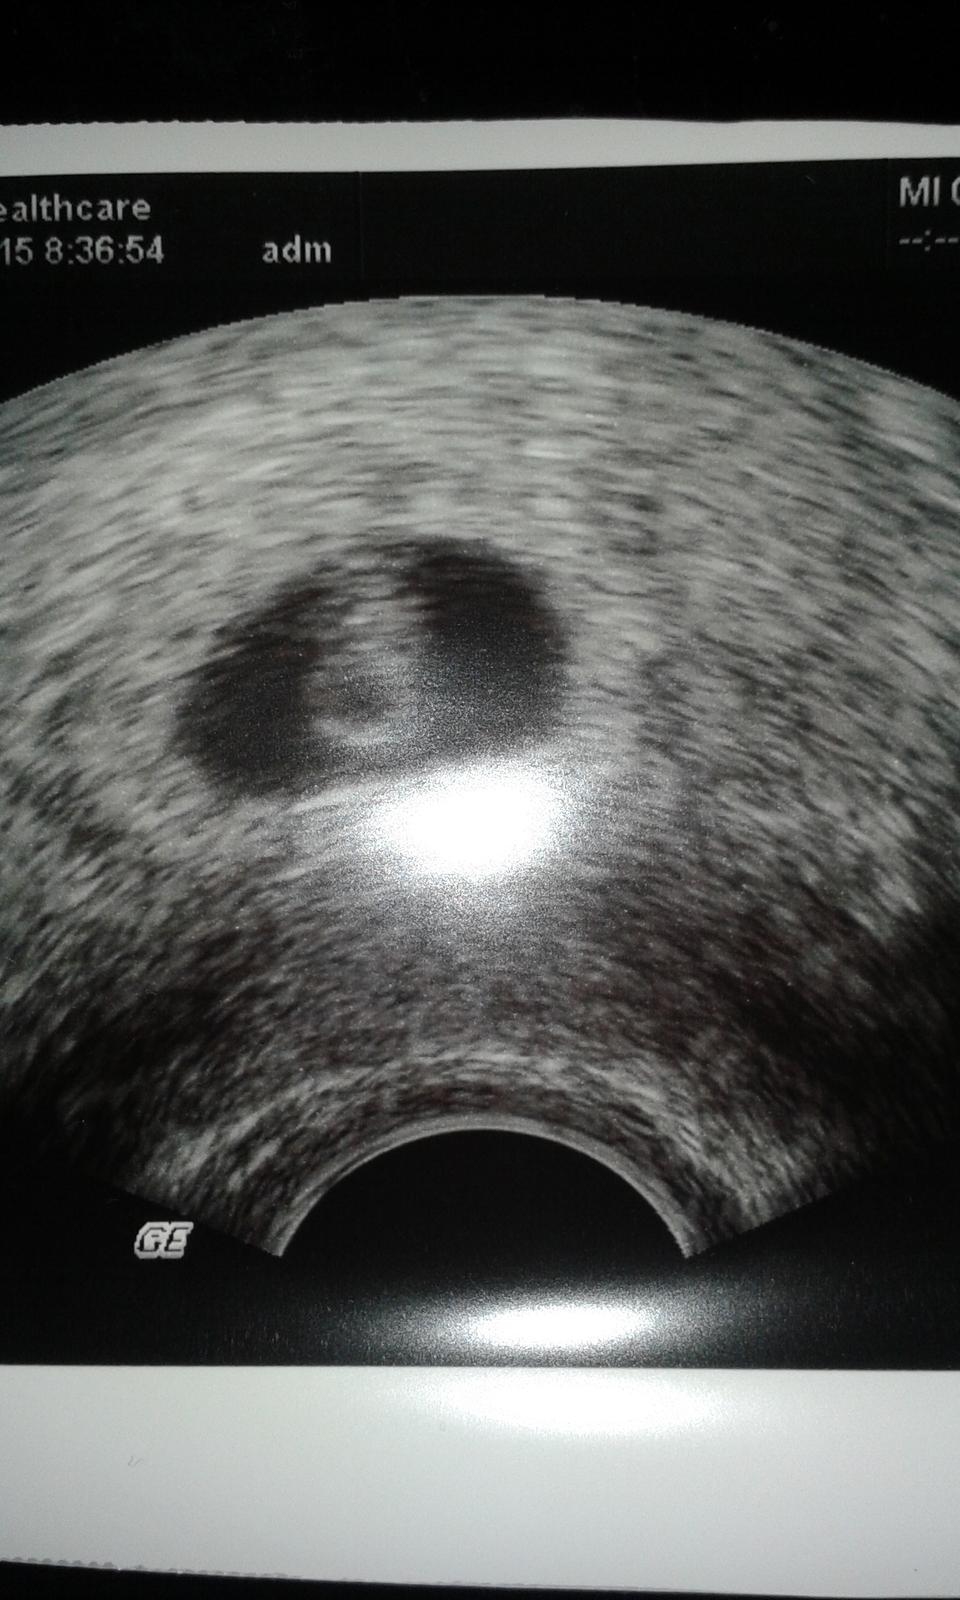

@lzii ahojky,dle tohto je to asi zatim gestacni vacek

@tynulkaxix ahooj takze je vsetkoo ok som rada ☺☺aj ti byva zle?nejake priznaky??? Prikladam moju foto z ultrazvuku 5tt+4 a mame 8mm